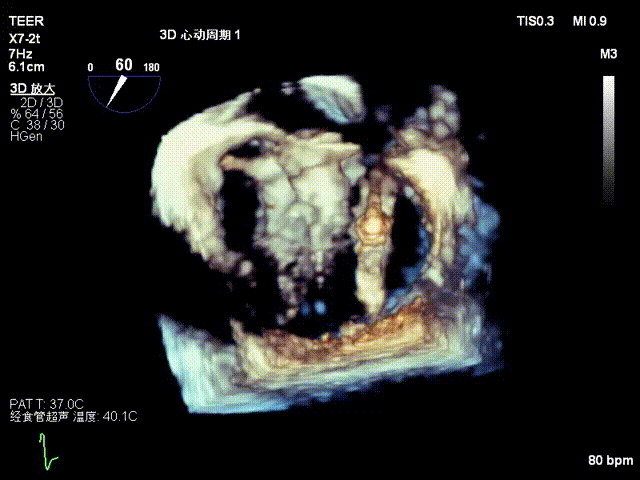

患者为73岁老年男性,经食道超声检查提示:急性二尖瓣腱索断裂合并反流,前叶长度:2.8cm,后叶长度:1.7cm,脱垂宽度:18mm,脱垂高度:8mm,瓣口面积:6.5cm²。

术前影像

3D

3D彩色